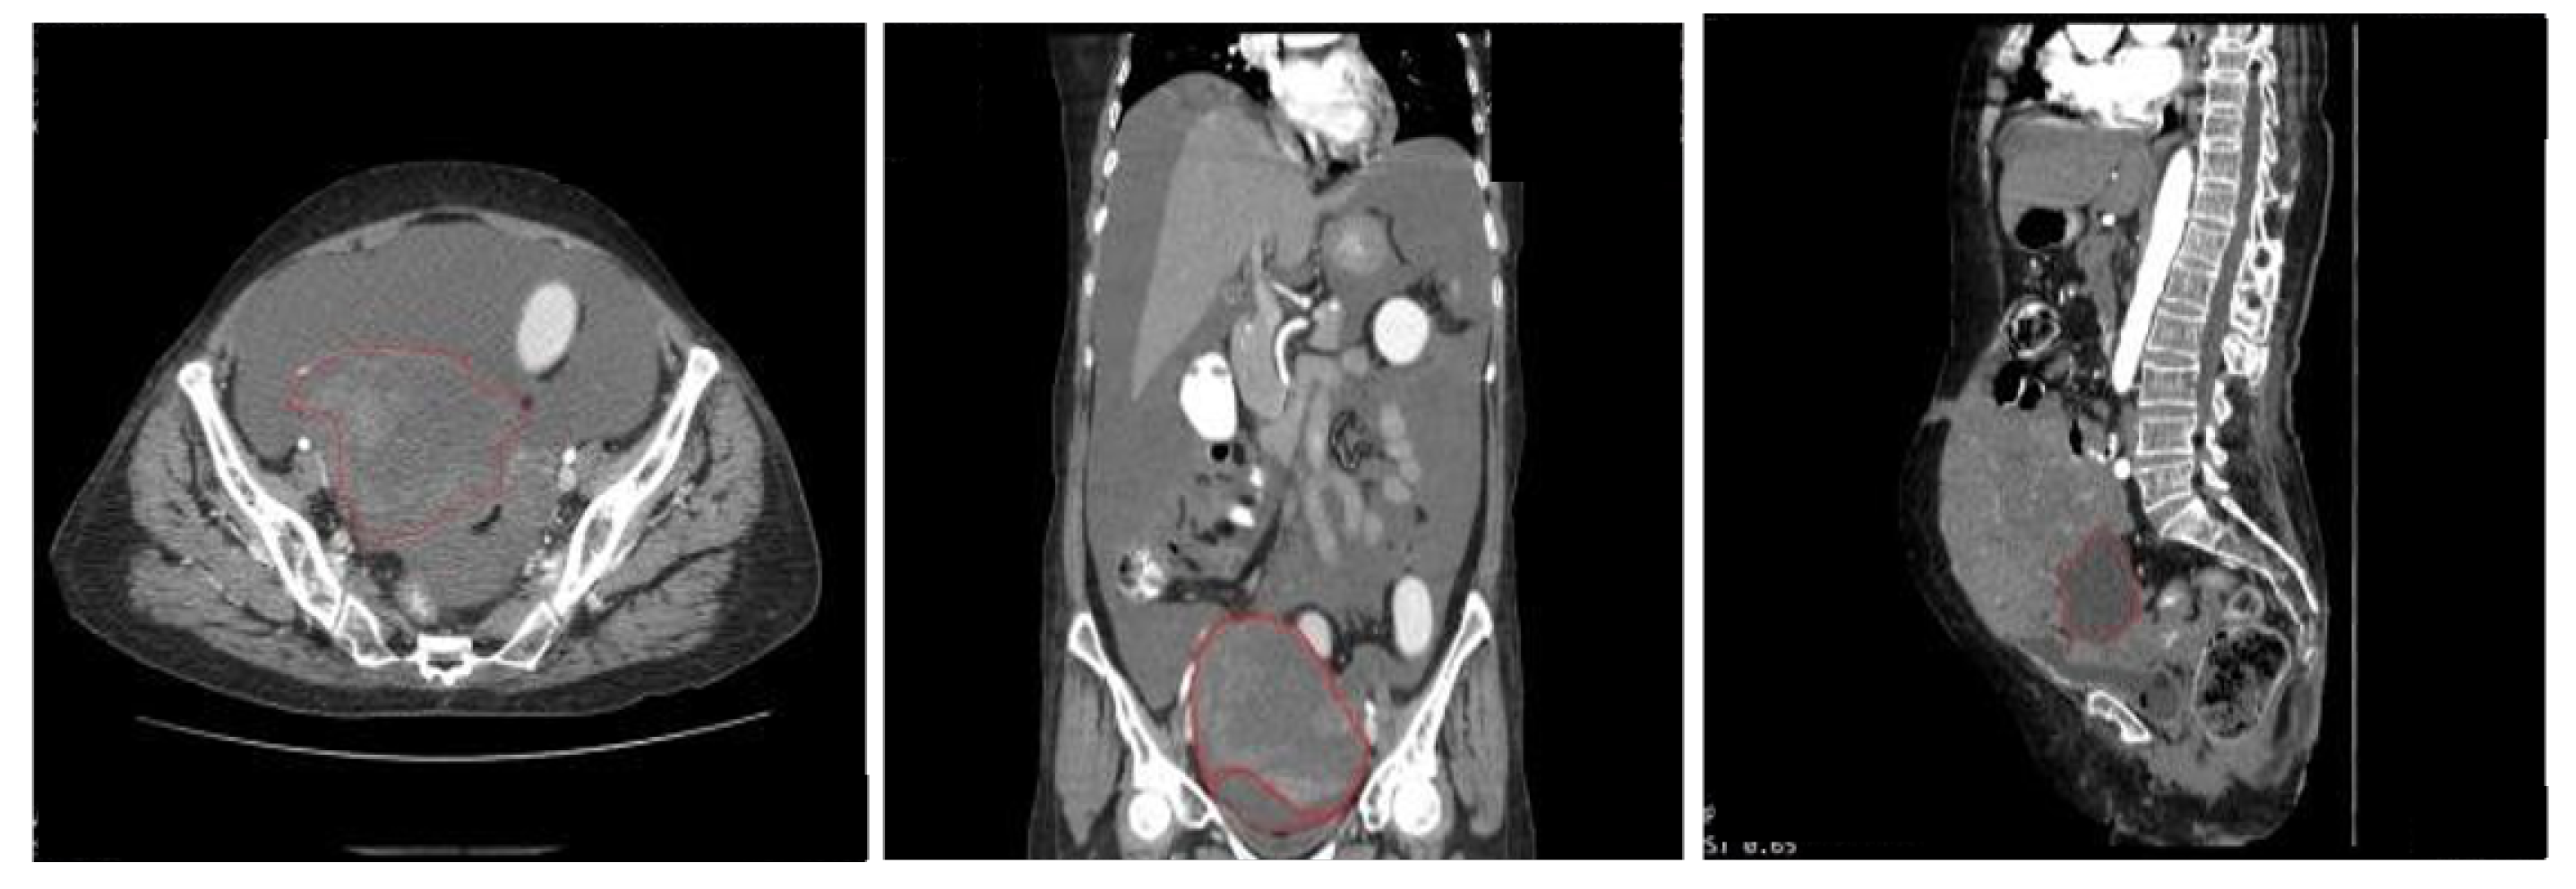

5.1. Data Source and Description

5.2. Data Preprocessing and Dataset Preparation for Training and Evaluation